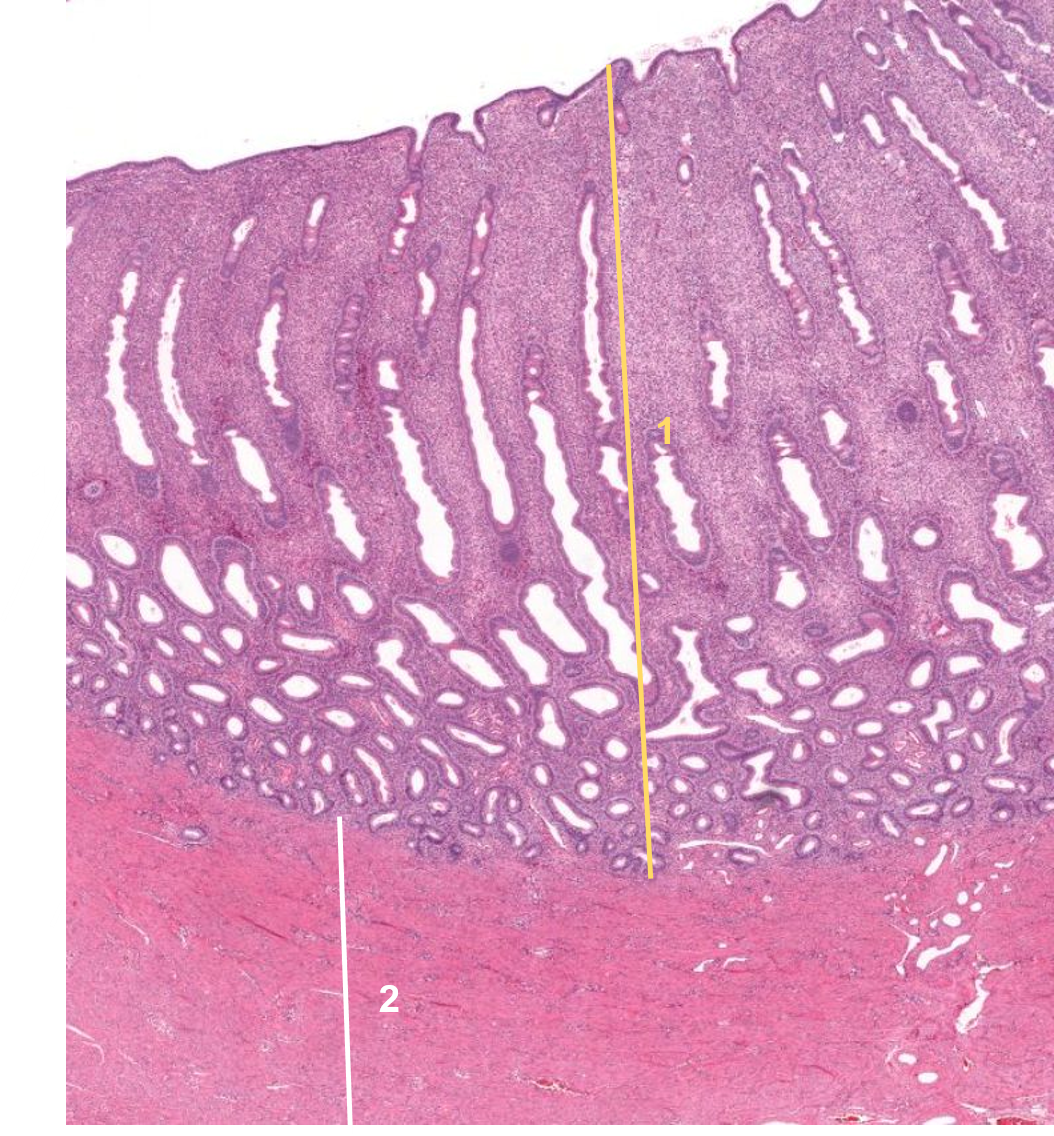

1: Cólon

2: Submucosa - Tecido conjuntivo laxo

Útero

1: Útero - endometrio

2: Miométrio